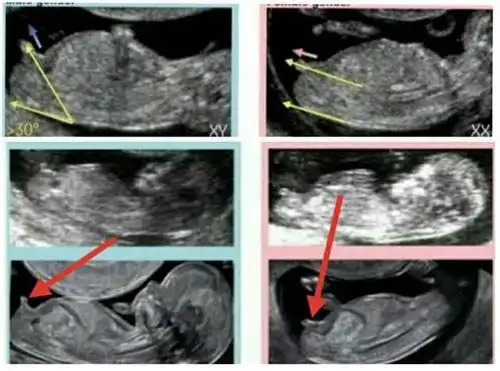

做b超过程中 如何分辨男孩or女孩

孕 周二维超声示胎儿男性外生殖器,呈「郁金香征」